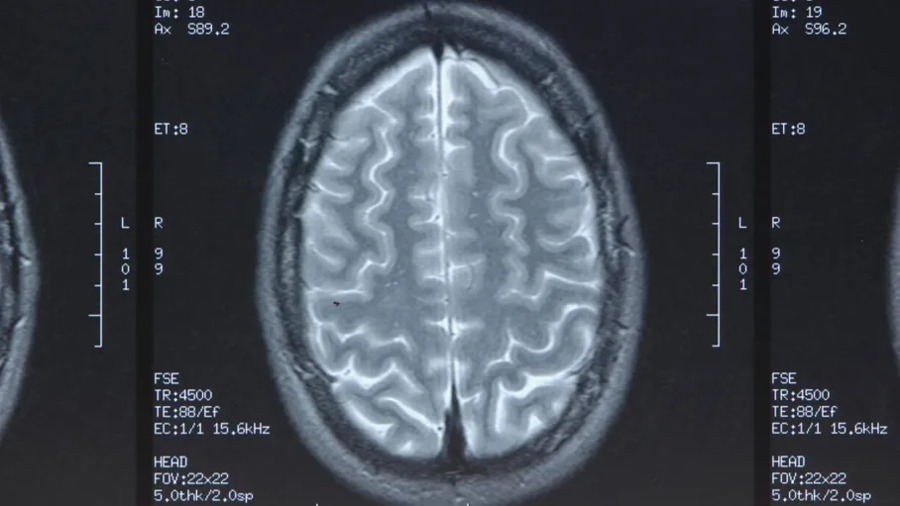

Современные методы диагностики и их ограничения

Для подтверждения смерти мозга врачи используют тесты, такие как проверка рефлексов ствола мозга или симптом Кантелли («головы и глаз куклы»). Однако эти методы не всегда применимы, например, при травмах шеи. В таких случаях прибегают к КТ-ангиографии или КТ-перфузии, которые оценивают кровоток в мозге. Исследование, проведенное в Канаде в 2024 году и опубликованное в Canadian Medical Association Journal, показало, что даже эти методы несовершенны. Чувствительность КТ-перфузии ствола мозга достигает 98,5%, но специфичность — лишь 74–92%. Это означает, что у 2 из 25 пациентов смерть мозга может быть диагностирована ошибочно.